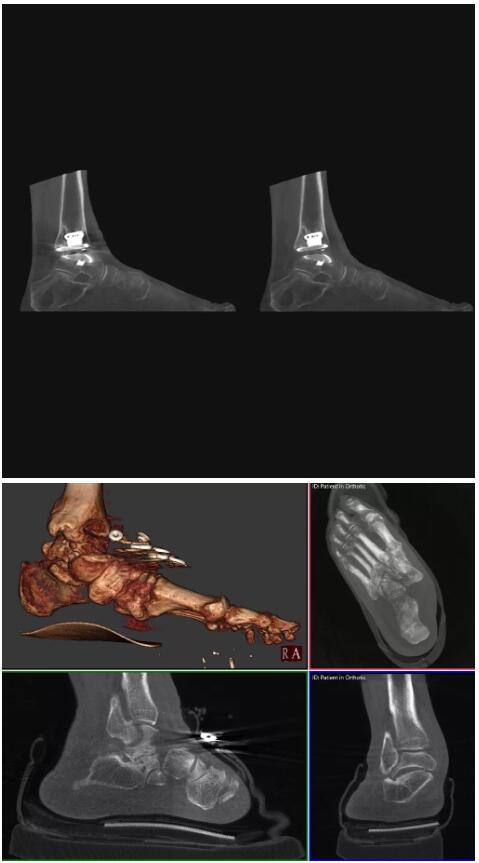

比如上面這款專用于足部和踝部掃查的CT成像系統(tǒng),患者在進行CT掃查時只需要站在上面即可,雙腳站或者單腳站都可以,當(dāng)然,如果患者不是那么方便站著做完CT掃查,也可坐在上面。

這款CT掃查系統(tǒng)自帶屏蔽裝置,它的體積非常小,僅需要極小的空間即可,并不像常規(guī)CT那樣需要一間單獨的檢查室。此外,這種CT掃查的速度非常快,僅需30秒左右可以完成檢查,輻射劑量相對常規(guī)的CT要少許多,尤其適合醫(yī)院的骨科使用。

而患者站著做足部或者踝部做CT檢查還有個好處是,可以檢查患者在負(fù)重的情況下,骨關(guān)節(jié)的真實情況,而躺著做CT掃查時未必能看出來。負(fù)重CT掃查特別是對于受傷的運動員或者舞蹈員來說意義更大,能夠更準(zhǔn)確地評估傷情,幫助他們盡早復(fù)原。

以下是這些“特立獨行”的CT所拍出來的圖像: